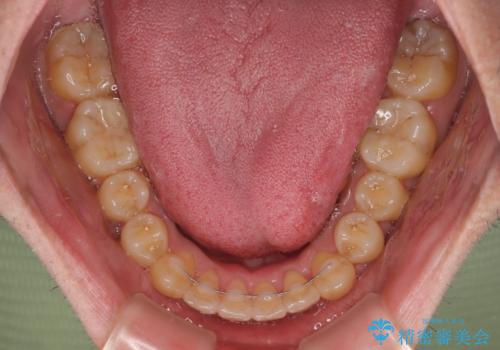

八重歯とクロスバイト 目立たないワイヤー装置で矯正治療

- 八重歯と前歯のクロスバイトを改善したいとのことで来院された患者様です。

マウスピース矯正での自己管理には自信がないとのことで、ワイヤー装置による矯正治療を行うこととしました。

デコボコの程度は強かったのですが、口元の突出感はなかったため、非抜歯矯正としました。